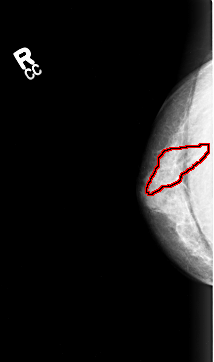

B_3003_1.RIGHT_CC

RIGHT_CC LINES 4336 PIXELS_PER_LINE 2560 BITS_PER_PIXEL 12 RESOLUTION 50 OVERLAY

FILE: B_3003_1.RIGHT_CC.OVERLAY

TOTAL_ABNORMALITIES 1

ABNORMALITY 1

LESION_TYPE CALCIFICATION TYPE FINE_LINEAR_BRANCHING DISTRIBUTION LINEAR-SEGMENTAL

ASSESSMENT 5

SUBTLETY 3

PATHOLOGY MALIGNANT

TOTAL_OUTLINES 1

BOUNDARY